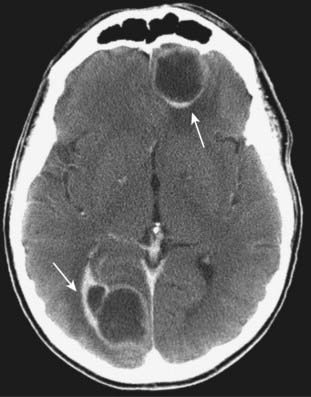

Metastases

image Solitary intraaxial masses are about evenly split between solitary metastases and primary brain tumors. About 40% of all intracranial neoplasms are metastases. Lung, breast, and melanoma are the most common primary malignancies to produce brain metastases.

imageRecognizing metastases to the brain

image Metastases to the brain are frequently well-defined, round masses near the gray-white junction.

image They are usually multiple, but can be solitary.

image They are typically hypodense or isodense on nonenhanced CT.

image With intravenous contrast, they can enhance, sometimes with a pattern of ring-enhancement.

image Most evoke some vasogenic edema, frequently out of proportion to the size of the mass (Fig. 25-28).

image

Figure 25-28 Metastases, contrast-enhanced CT.

About 40% of all intracranial neoplasms are metastases. They typically produce well-defined, round masses near the gray-white junction and are usually multiple. With intravenous contrast, they can enhance, sometimes demonstrating ring enhancement (solid white arrows). Lung, breast, and melanoma are the most common primary malignancies to produce brain metastases. This patient had lung cancer.